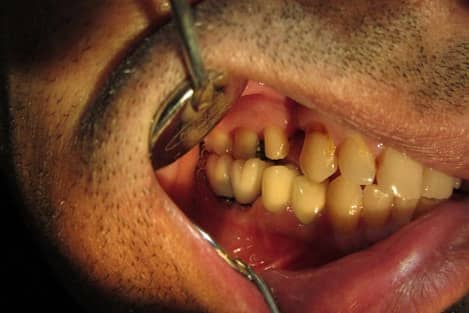

Dental Dam Isolation